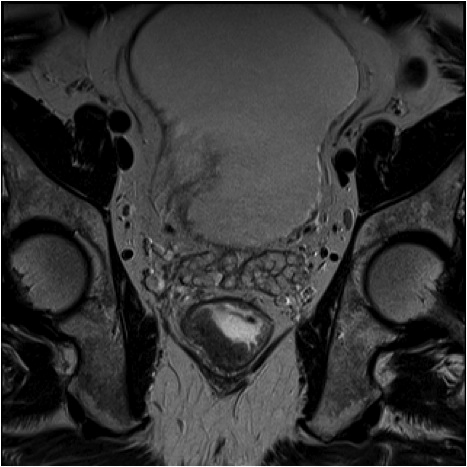

Fig1. Pacient cu neoplasm rectal stadiul IIIC (T3; N2; M0) confirmat bioptic, adenocarcinom mixt G2

a-d imagini T2 ponderate în plan sagital, oblic axial și oblic coronal – masă tisulară dezvoltată superior de joncțiunea anorectală, lateral dreapta, cu minimă extensie la nivelul grăsimii mezorectale și limfoganglioni mezorectali cu diametru de până la 10 mm;

e,f) restricție de difuzie la nivelul tumorii rectale și a doi ganglioni mezorectali

g,h,i) priză de contrast moderată la nivelul tumorii rectale și al ganglionilor mezorectali

j) reconstrucții curbe în planul adevărat al rectului, cu evidențiere mai bună a fasciei mezorectale